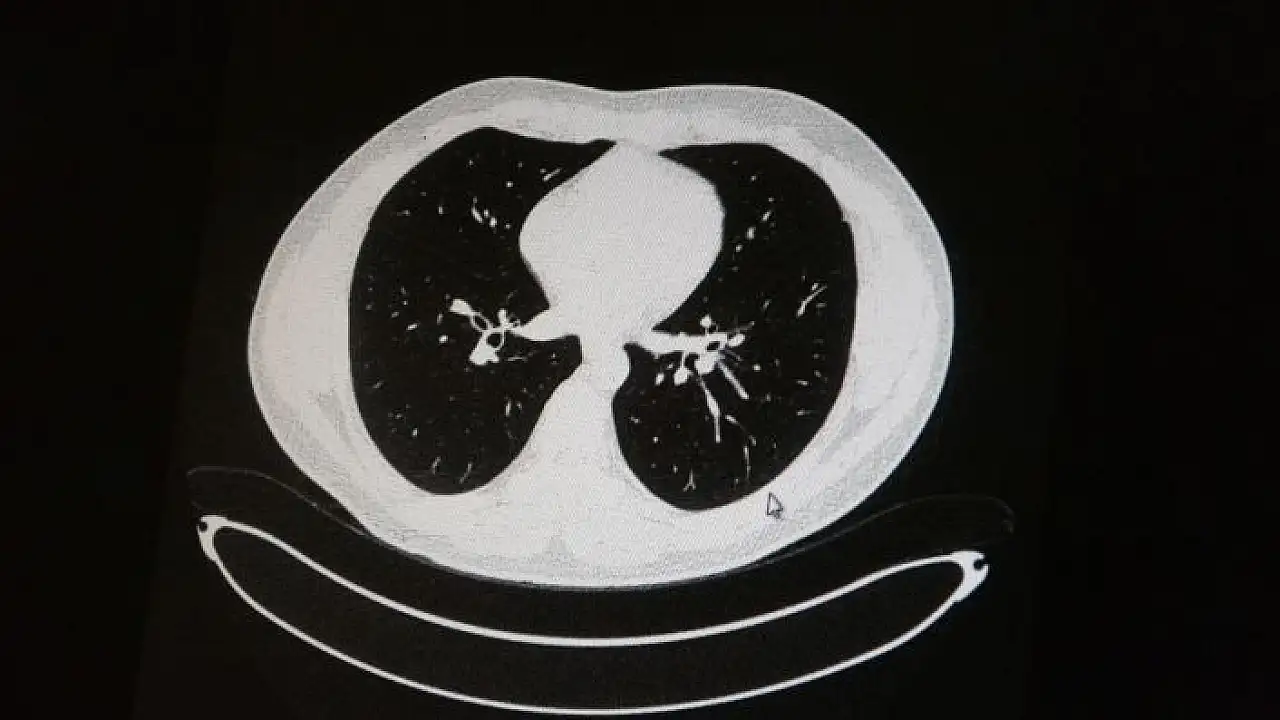

Elazığ´da öksürük, halsizlik, yorgunluk ve çabuk yorulma gibi şikayetlerle hastaneye başvuran ve korona virüs tespit edilen 2 genç hastadan aşısız olanının tomografi sonuçlarında virüsün akciğerlerde zatürreye sebebiyet verdiği görüldü. Aynı şekilde aşı olup korona virüs hastalığına yakalanan bir başka genç hastanın bilgisayarlı akciğer tomografisinde akciğerinde herhangi bir sorunun olmadığı belirlendi.

Medical Park Elazığ Hastanesi Göğüs Hastalıkları Uzmanı Dr. Cebrail Azar, geçtiğimiz yıla oranla yoğun bakımda yatan hastaların yaş ortalamasının 65´ten 35´lere kadar düştüğüne dikkat çekti. Genç olduğu halde aşı olmayanlarda hastalığın ağır seyrettiğini ifade eden Uzm. Dr. Azar, "Ben gencim, benim bağışıklık sistemim kuvvetli" diyen genç bir hastanın akciğerlerinde ciddi lekelenmelerin olduğunu ve korona virüs zatürresi olduğunu gördüklerini belitti. Uzm. Dr. Azar, aynı şekilde aşı olup korona virüs hastalığına yakalanan bir başka genç hastanın akciğer tomografisinde akciğerde herhangi bir sorunun olmadığını ve hastanın durumunun iyi olduğunu gözlemlediklerini kaydetti. Uzm. Dr. Azar, sürekli şahit oldukları "Keşke biz aşı olsaydık" sözünü bir daha duymamak için herkesi aşı olmaya davet etti.